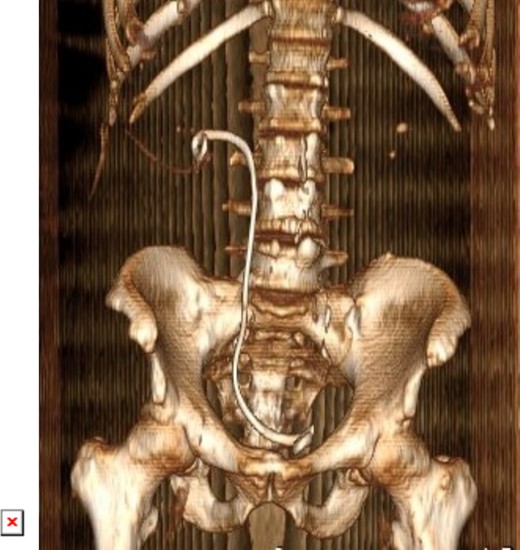

On physical examination, he had normal vital signs, no fever, and exhibited mild tenderness in the suprapubic area and right costovertebral angle. The results of the laboratory tests were normal, and the serum creatinine level was 0.8 mg/dl. Urine culture was negative for bacteria. Preoperative abdominal and pelvic ultrasound revealed two right renal stones, one measuring 4 cm in the upper pole and 2 cm in the lower pole with mild hydronephrosis, along with a large bladder stone measuring 6 cm, and a shadow of a double J stent. A computed tomography (CT) scan confirmed the presence of a 4 cm upper pole renal stone, a 1.8 cm lower pole renal stone, significant proximal pigtail calcification with mild hydronephrosis (Fig. 1A and B), and a 6 cm bladder stone deeply embedded in the distal pigtail (Fig. 2A and B). Additionally, small intrarenal stones were observed on the left side, along with a proximal ureteric stone measuring 8 mm by 9 mm with mild hydronephrosis.

Non-contrast CT scan showed giant bladder stone profoundly embedded in the distal pigtail of the DJ stent.

3D constructed image of postoperative low dose non-contrast CT scan showing stone clearance and newly inserted DJ stent in-situ.